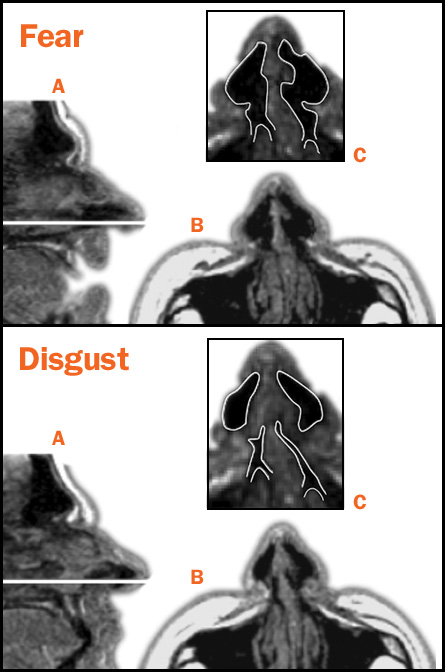

At least two emotional expressions, those of fear and disgust, first served to moderate sensations coming in from the outside world, researchers report online June 15 in Nature Neuroscience. They show that terrified eyes widen and nostrils flare to monitor the surroundings, and the nose crinkles in disgust to impede nasty odors.

Researchers measured the field of vision for study participants who pretended to be freaked out or grossed out. When participants put on a fearful face, their eyes widened and they were able to detect lights flashing above their head. When acting disgusted, they squinted and couldn’t see the flashing lights. Using MRI, the researchers measured how much air the participants inhaled under each facial condition. Air intake increased when people wore a fearful expression and decreased when they looked revolted. The results support the idea that fearful faces observe more of the surrounding atmosphere — by seeing farther and sniffing deeper, the researchers say. In contrast, disgusted faces block the senses from detecting the environment.